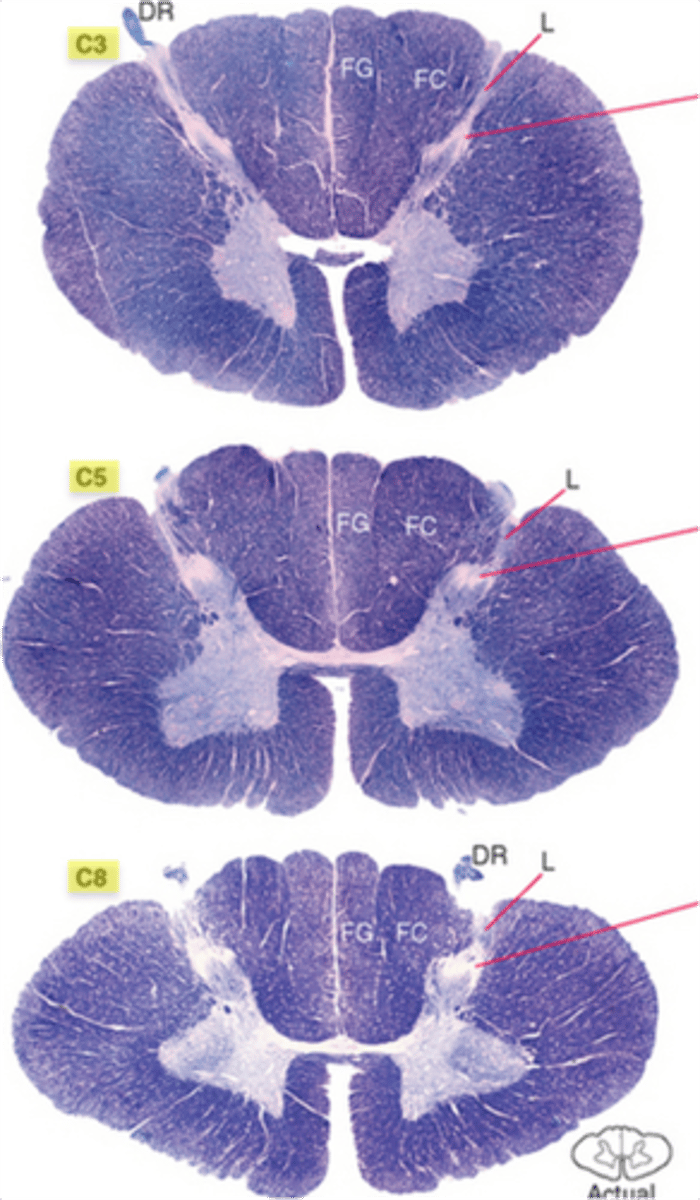

which division of the spinal cord is oval in shape, has a large amount of white matter, and includes an enlargement in the lower region?

cervical; cervical enlargement at C4-T1

which division of the spinal cord is round, with small anterior and posterior horns, and lateral horns present?

thoracic